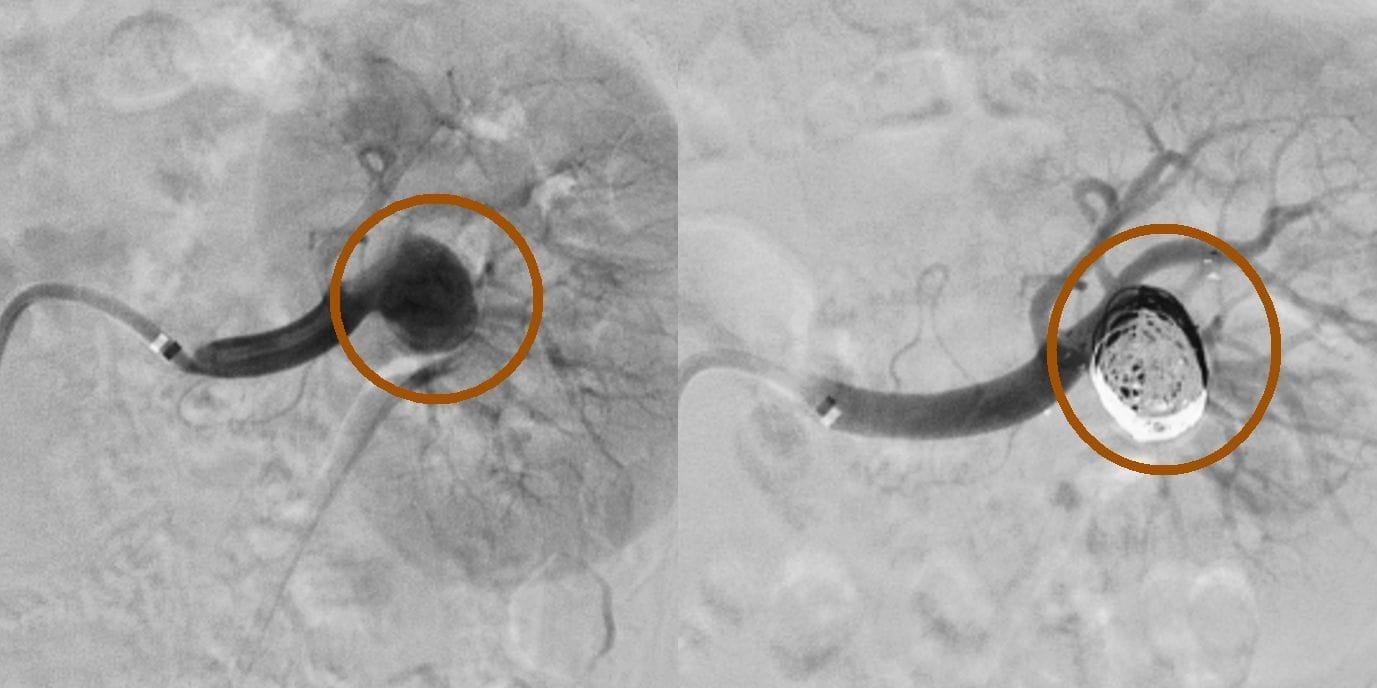

Die Methode findet insbesondere bei blutungsbedingten Erkrankungen Anwendung. Blutungen und Tumore in verschiedenen Organen des Körpers können durch Embolisation kontrolliert werden. Zu den schwerwiegenden Beschwerden, die Patienten erleben, gehören auch lebensbedrohliche Zustände wie zerebrale Aneurysmen und arteriovenöse Malformationen.

- Zerebrale Aneurysmen

Welche Techniken werden bei der Embolisation angewendet?

- Metall-Coils: Kleine Geräte, die aus rostfreiem Stahl oder Platin hergestellt sind und eine präzise Platzierung ermöglichen.

Fallbeispiele